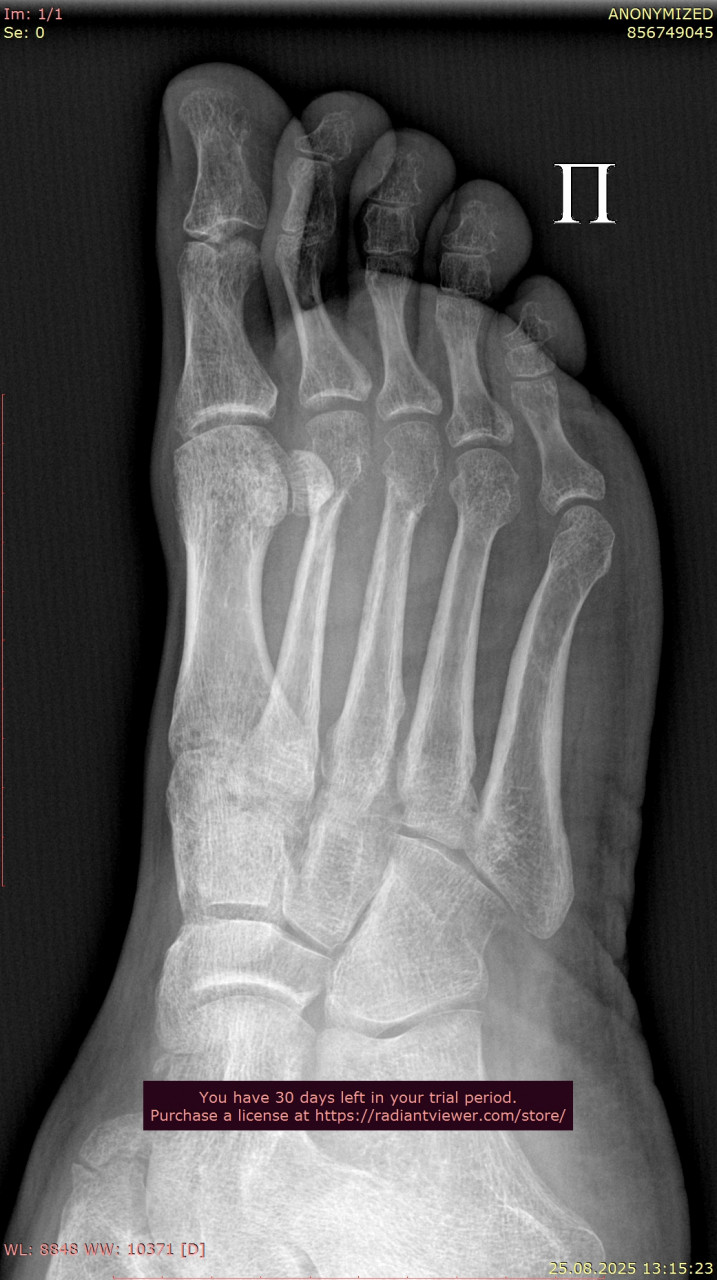

Сравнивая ваши снимки от 23.06 и 25.08:

- Линии переломов на костях стопы и области голеностопного сустава больше не прослеживаются чётко, видна формирующаяся костная мозоль – это признак заживления.

- Смещения отломков нет, контуры выровнены, что говорит о правильном срастании.

- Для срока 2 месяца после перелома динамика положительная, основные признаки консолидации присутствуют. Обычно к этому времени разрешают постепенную нагрузку, но полное снятие опоры (ходьба без костылей, тростей) должно быть постепенным и согласовано с вашим травматологом.

По поводу артроза, на рентгене действительно заметны начальные изменения в суставах стопы (сужение суставных щелей, небольшие краевые разрастания), но они умеренные и для 38 лет не критичны. Такие изменения часто встречаются после травм и нагрузок, но выраженного деформирующего артроза нет.

По вашим новым снимкам от 28.07 и контрольным от 25.08 признаков несращения или смещения нет т.к переломы в области стопы и голеностопного сустава консолидируются, костная мозоль выражена, контуры ровные. То есть прочность костей уже достаточна, чтобы постепенно начинать ходьбу без ходунков. То, что вы пока ставите ногу без активного сгибания пальцев, допустимо и так обычно и бывает на этапе ранней нагрузки. Постепенно с помощью ЛФК и разминки подвижность пальцев и стопы восстановится. Перегрузки голеностопа при аккуратной ходьбе на полной стопе сейчас не будет, наоборот  умеренная нагрузка нужна для правильного ремоделирования костной ткани.